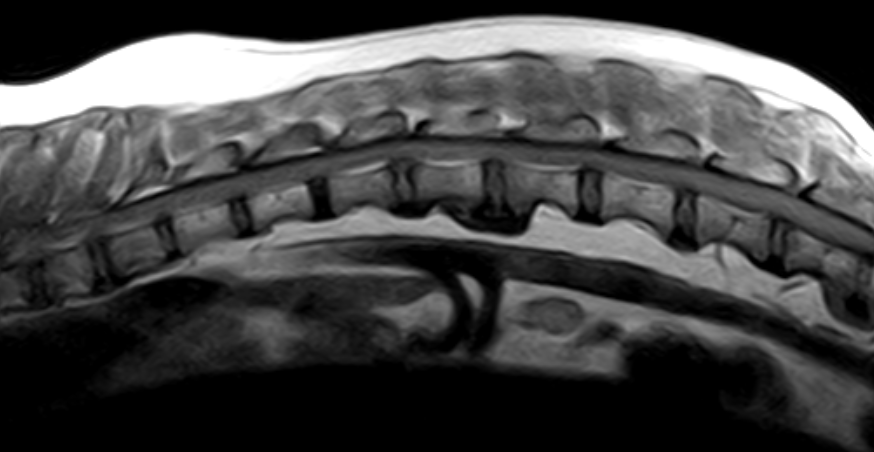

Imágenes de Calidad Premium

VET MR GRANDE

IMÁGENES CLÍNICAS

En la sección de imágenes clínicas, destacamos la precisión y claridad de nuestros estudios, respaldados por un equipo de radiólogos especializados en medicina veterinaria. Nos enorgullece ser un aliado confiable para veterinarios y clínicas, brindando un servicio rápido y eficiente para ayudar en la toma de decisiones clínicas fundamentadas.